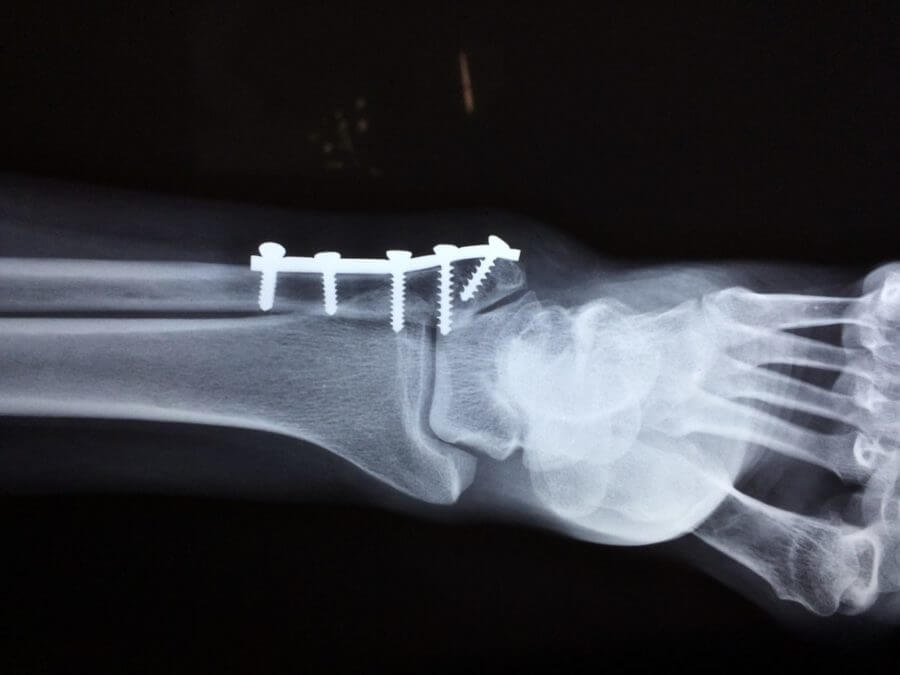

- Properly set bones so that pain is reduced after the surgery

- Repair fractures through correct placement of hardware

Hand and Wrist Surgery Negligence

Surgery to the wrist and hand requires working around a lot of delicate bones and tendons. Small instruments like cameras and drills make these arthroscopic surgeries more effective than ever before. However, it’s important to know that hand surgery should always be done by a hand surgeon, whether an orthopedic surgeon or a plastic surgeon with special training. There is not a specific board certification for hand surgery. Without proper experience, surgeons may alter the wrong bones in the hand or wrist. They also may not know how to use the surgical tools or be experienced enough for a complex procedure. If you are preparing for a hand surgery don’t be afraid to ask questions about your surgeon’s experience and the outcomes of their past procedures.